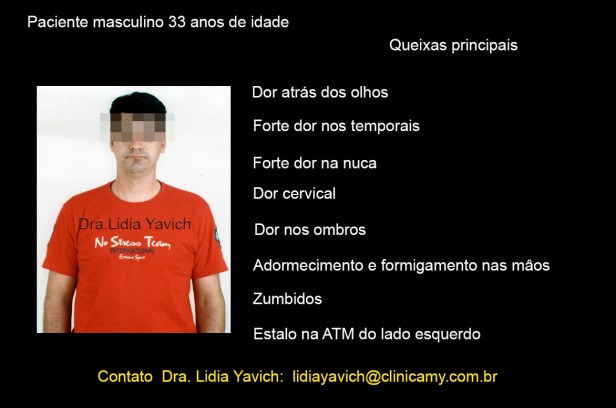

Paciente masculino de 33 anos de idade se apresenta na consulta relatando fortes dores nos temporais, dor no pescoço, dor facial inespecífica, dor nos ombros, zumbidos e relata também que vem sentindo adormecimento e formigamento nas mãos.

O paciente também se queixa de estalos na articulação temporomandibular do lado esquerdo. Relata sensação de diminuição auditiva, mesmo que a audiometria apresenta-se dentro dos valores normais.

Refere tremores musculares na região das bochechas, e dificuldade constante para abrir a boca.

O paciente não apresenta limitação na abertura bucal, mas para abrir desvia a mandíbula para o lado esquerdo.

Sente dor para mastigar alimentos duros, refere que só consegue se alimentar com alimentos moles.

Relata que qualquer refeição implica esforço e não uma atividade agradável, mesmo com alimentos que ele gosta.

Refere bruxismo e apertamento dentário. Diz que sente também dificuldade para deglutir.

O paciente apresenta um perfil retrusivo, mas isso NÃO FOI O MOTIVO DA CONSULTA, o paciente não estava preocupado pela estética, mas sim com A DOR.